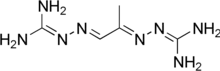

| Other names | 2-[[(1E)-1-(Diaminomethylidenehydrazinylidene)propan-2-ylidene]amino]guanidine |

| Formula | C5H12N8 |

| Molar mass | 184.207 g·mol−1 |

Mitoguazone (also known as methylglyoxal bis(guanylhydrazone) or MGBG) is a drug used in chemotherapy.[1]